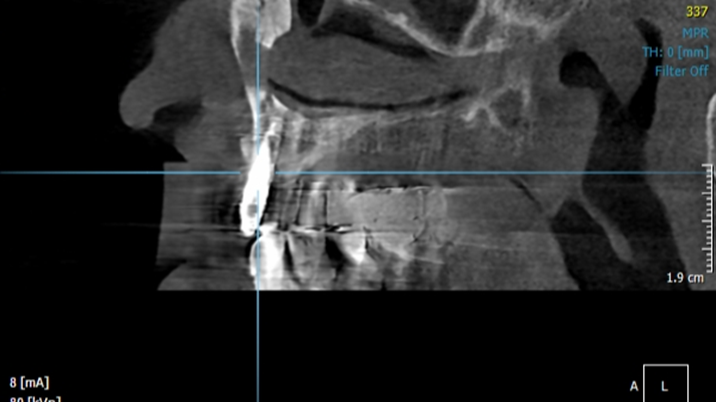

Clinical case: Peri-implantitis treatment case using titanium or NiTi brush

- Courtesy of Dr. Dae-Hee Lee, South Korea -

Dr. Dae-Hee Lee,Maxillary Anterior,Peri-implantitis,Bone regeneration,Aesthetic zone,#21,#22,GBR,Titanium Brush Set